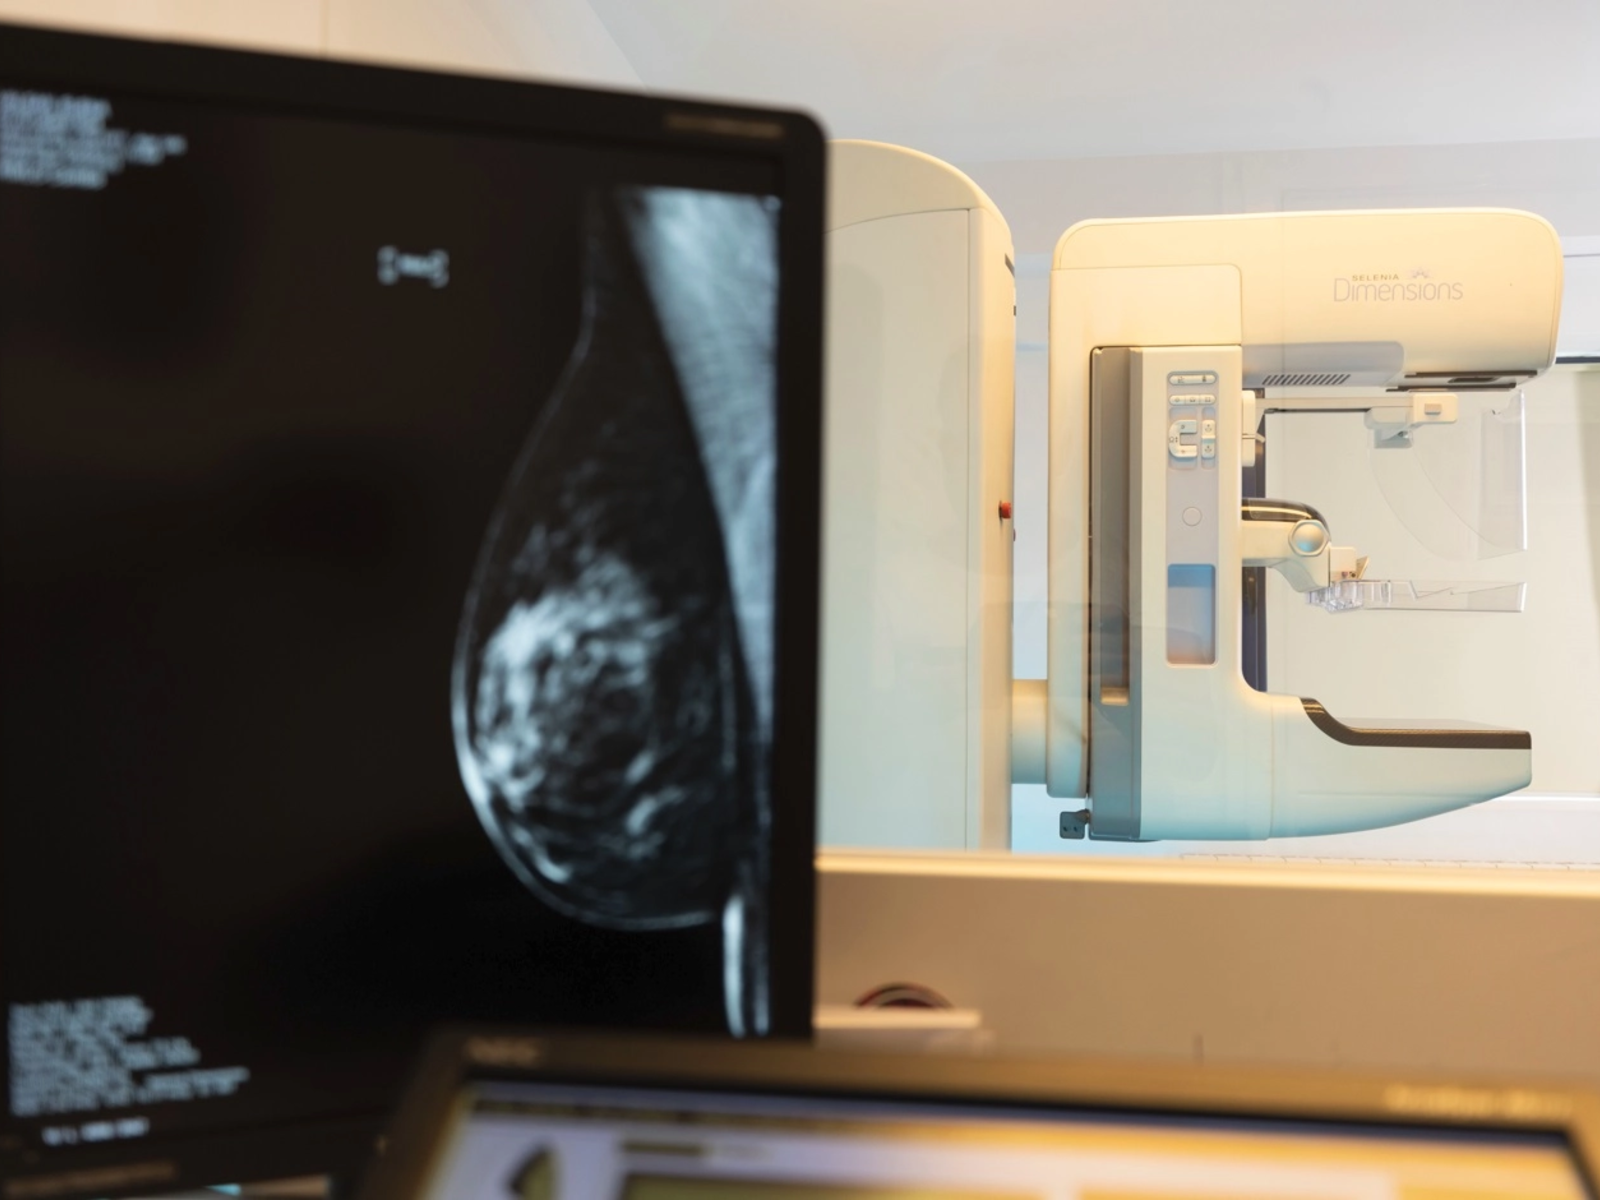

În prezent, pacientele au acces la mamografie digitală cu tomosinteză, care oferă numeroase avantaje comparativ cu o mamografie clasică, asigurând un diagnostic foarte precis al cancerului, cu mai puține rezultate fals pozitive sau fals negative.

Investigația durează mult mai puțin și implică mai puțin disconfort pentru paciente, pentru că sânii sunt presați doar câteva secunde. Doza de radiații este foarte redusă, prin urmare nu există un risc din acest punct de vedere. Imaginile obținute în timpul scanării sunt stocate digital și pot fi consultate ulterior, iar aparatul de tomosinteză permite o reconstrucție tridimensională a structurii sânului. Astfel, imaginile sunt mult mai detaliate, la o rezoluție superioară și cu mai puține interferențe, iar leziunile benigne și cele maligne sau suspecte sunt mai ușor de diferențiat.

La SANADOR, pacientele au acces la consultații asigurate de medici foarte experimentați, specializați în afecțiunile sânului și la toate investigațiile imagistice necesare pentru screeningul și diagnosticul cancerului de sân. În Clinica SANADOR Victoriei Corp A sunt disponibile mamografii digitale cu tomosinteză realizate cu echipamentul de ultimă generație Selenia Dimensions 3D Hologic, unul dintre cele mai performante aparate disponibile în prezent.